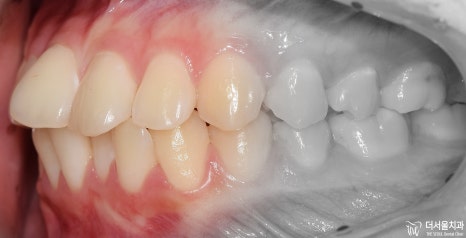

측면에서는 확연히, 돌출입 형태를 확인하실 수 있습니다. 이렇게 앞니들이 앞으로 뻐드러져

있는데 심미선을 기준 으로 봤을 때 입술의 위치가 그대로 예쁜 곳에 있는 걸 보면

연조직이 얇아서 가능하다라는 것을 추측할 수 있겠네요.

아울러, 이 분의 경우에는 비발치 교정 으로 치료를 하길 원하셨었습니다.